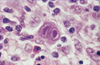

A 14 year old girl comes to the clinic with a fever, sore throat and fatigue for the past month. On physical exam you note posterior cervical lymphadenitis. What would you expect to see on blood smear?

She has infectious mononucleosis from EBV. You would see atypical lymphocytes on blood smear because of the reactive T cell response to the viral infection.

EBV is transmitted orally. You 1st get IgM antibodies against the capsid, then you form IgG. Infection causes atypical (really large) cytotoxic T and NK lymphocytes activity against polyclonal B cell proliferation (hence the lymphadenopathy).

A 14 year old girl comes to the clinic with a fever, sore throat and fatigue for the past month. On physical exam you note posterior cervical lymphadenitis and hepatosplenomegaly. Her peripheral blood smear is shown below. Why do you think this is a reactive condition vs. a neoplastic condition?

Note the atypical lymphocyte skirting around the RBCs, this is not seen in neoplastic states, often seen in reactive states.